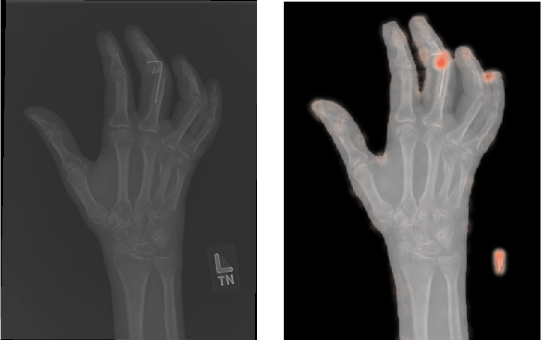

4.2 Qualitative Results

In addition to the numerical results we also showcase some qualitative results. For all methods with reconstruction loss, i.e. all AE as well as -GAN, we can generate heatmaps visualizing the pixel-wise losses. Thereby, we can highlight regions that could not be reconstructed well. Following our assumption, these regions should be the anomalous regions. In Figure 5, we can see prototypical examples produced by CAE. The upper image shows a hand contained in a study which was labeled as normal. We can see that the reconstruction error does not occur concentrated, but is rather spread widely across the hand. The maxima seem to occur around joints, which due to their more complex structure are likely to be harder to reconstruct. Compared to the lower image, which shows a study labeled as abnormal, we see a clear highlighting at the middle finger. Visible also for a non-expert, we can spot metal parts in the X-ray image at the very same location. For those anomalies which could be validated by a person without a medical background, the highlighted regions seem to correspond largely to those anomalous regions.